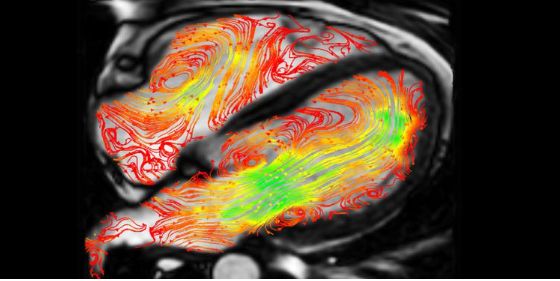

We work to understand and treat cardio metabolic diseases, a number of cardiac and circulatory disorders, linked to comorbidities such as diabetes or obesity. We view cardiometabolic disease as whole body and whole life problems that adversely affect wellbeing, societal contribution and life expectancy. We particularly focus our research on understanding the pathobiology of cardiovascular disease and how this is exacerbated by the comorbidity of type 2 diabetes. This deadly combination can reduce life expectancy by up to 15 years and is highly prevalent in the north of England. Our integrated teams of fundamental, data and clinical scientists work across university and hospital settings with the aim of helping people with, or at risk of, cardio metabolic disease. We work in partnership with patient and public involvement and engagement (PPIE) groups to ensure what we do is relevant to the community we serve.

We are interested in how disturbances in physical and metabolic homeostasis lead to related disorders including atherothrombosis, heart failure and vascular disease. We are further interested in how these disorders are phenotypically distinct where they have the added burden of diabetes. We hope that, informed by new knowledge, we can develop and implement new treatments and diagnostics.

We approach the heart, blood vessels, blood and metabolic organs as interacting components of a complex integrated body system that is shaped in its structure and function by metabolic events throughout life, from the embryo to old age. Our work encompasses the spectrum of scale from molecular and cellular studies of cardiovascular biology, organ and systems biology, animal models of disease, through to diagnosis and interventional trials.